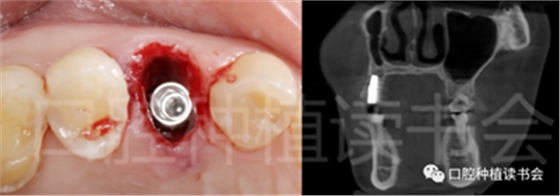

圖1 無(wú)法保留的上頜隱裂后牙,拔牙后即刻種植。

后牙區(qū)或者是非美學(xué)區(qū)即刻種植,對(duì)于患者和臨床醫(yī)生而言,存在一些明顯的優(yōu)勢(shì);比如更小的外科創(chuàng)傷、更短的愈合周期、更少的椅旁時(shí)間、更高的患者接受度以及更低的治療費(fèi)用等。除此之外,在上頜后牙區(qū)即刻種植還可以減少上頜竇的氣化現(xiàn)象【Sharan等.2008】;但并非所有的后牙位點(diǎn)都適合即刻種植,后牙區(qū)即刻種植對(duì)醫(yī)生的技術(shù)和經(jīng)驗(yàn)要求更高;由于解剖等諸多條件的差異,美學(xué)區(qū)即刻種植的臨床注意事項(xiàng)與后牙區(qū)即刻種植存在諸多不同之處;與本文旨在通過(guò)詳細(xì)的文獻(xiàn)回顧及臨床案例對(duì)后牙區(qū)即刻種植治療提供臨床參考。